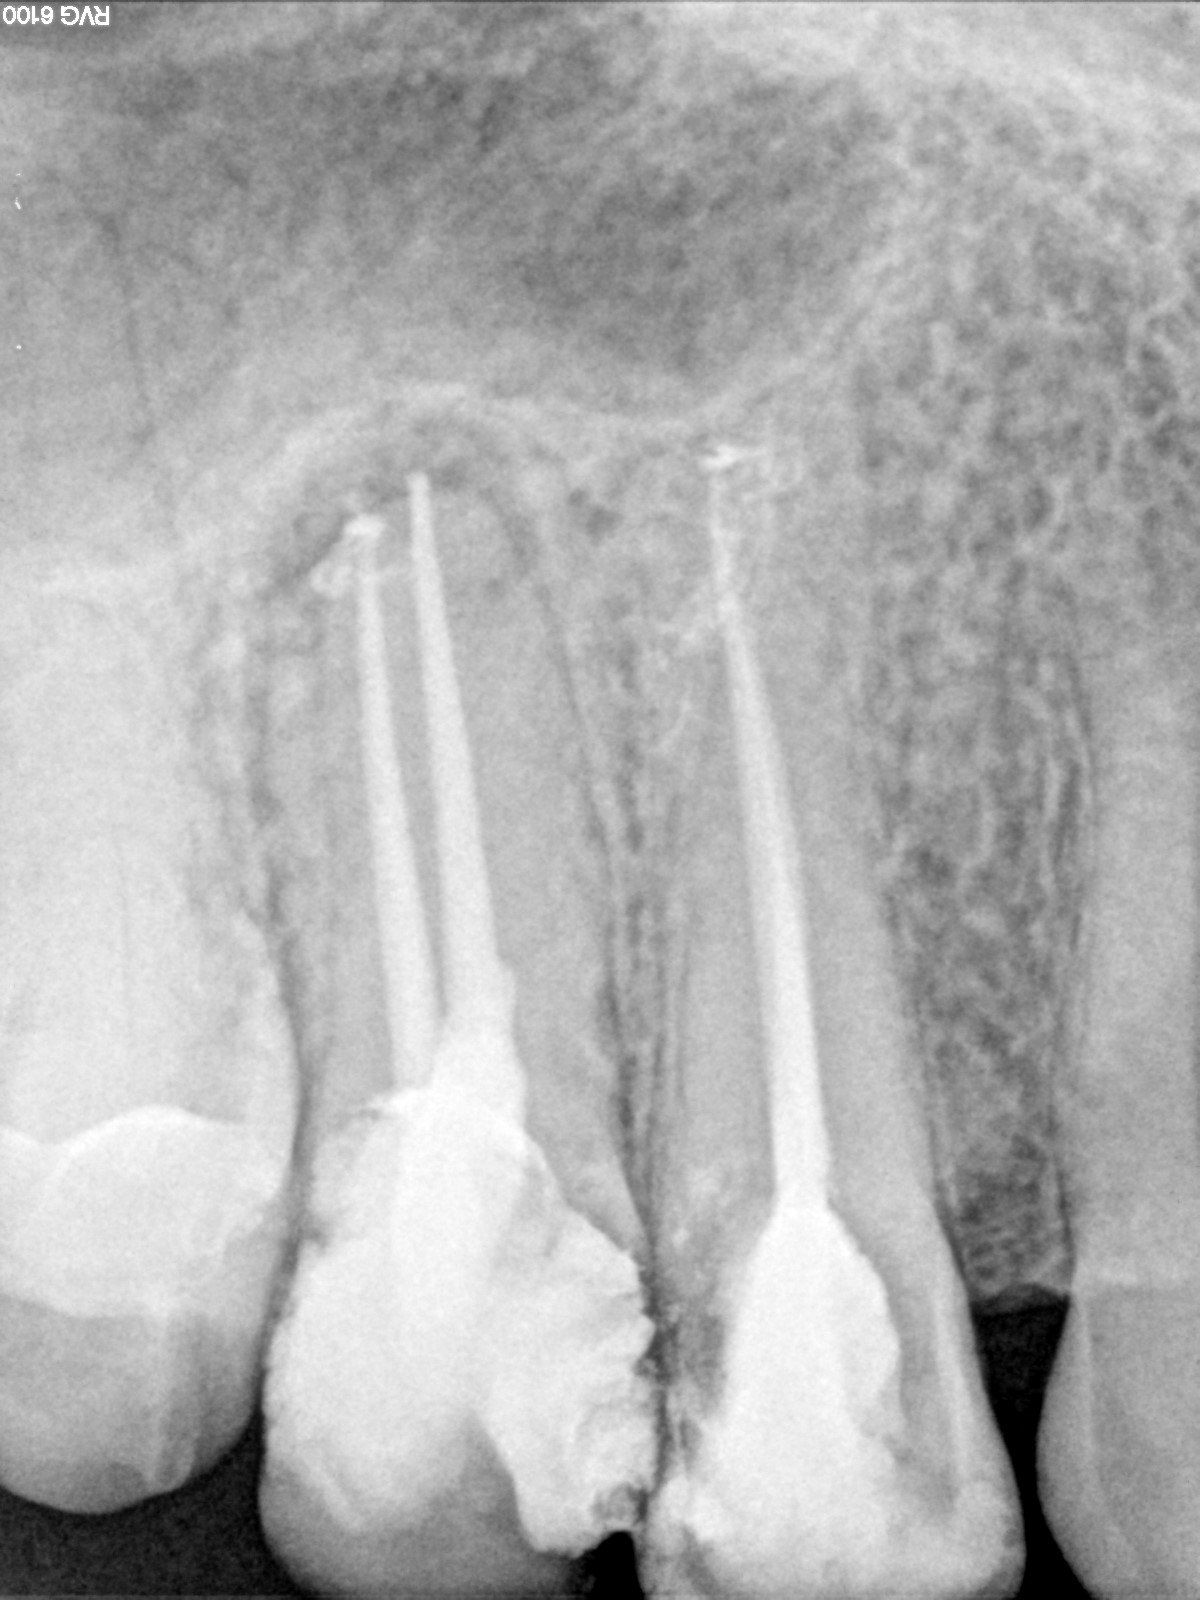

Endodonzia

Tra le mie competenze ci sono quelle specifiche per il settore dell’endodonzia.

Si tratta di una branca dell'odontoiatria che ha come principale obiettivo quello di procedere alla terapia di patologie che colpiscono l'endodonto ossia quello spazio presente all'interno dell'elemento dentario.

L'endodonzia è importantissima perché consente di prevenire ed eliminare dolori poiché, nella polpa dentaria, son presenti vasi e terminazioni nervose.

Tutto questo viene affrontato con le più moderne tecniche che permettono minima invasività e risultato in tempi ristretti.